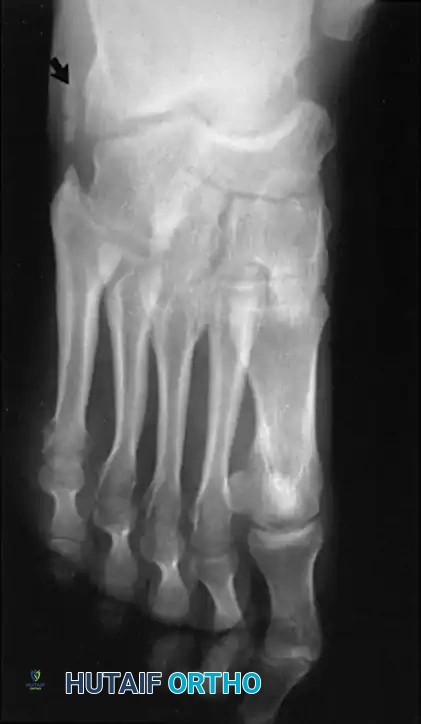

Radiographic Evaluation

Brockway’s 1940 axiom remains true: "Cavus feet should never be operated upon until radiographs with the patient standing have been taken."

Standard weight-bearing anteroposterior (AP) and lateral radiographs of the foot, along with a weight-bearing AP of the ankle, are required.

Key Radiographic Parameters:

* Meary’s Angle (Talus-First Metatarsal Angle): Normally 0 degrees. In a cavus foot, the angle is convex upward (apex dorsal), indicating midfoot/forefoot equinus.

* Calcaneal Pitch: Normally 15 to 20 degrees. In a cavus foot, it is significantly increased (>30 degrees).

* Hibbs Angle: The angle between the longitudinal axis of the calcaneus and the first metatarsal. It approaches 90 degrees in severe cavus (normal is ~140 degrees).

* Talonavicular Coverage: Assessed on the AP view to quantify midfoot adduction.

Fig. 7: Standing lateral radiograph demonstrating an increased calcaneal pitch and a severe apex-dorsal Meary's angle.